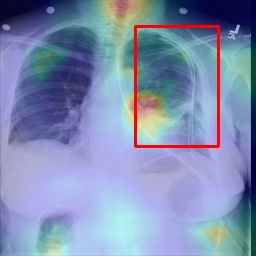

Deployments of artificial intelligence in medical diagnostics mandate not just accuracy and efficacy but also trust, emphasizing the need for explainability in machine decisions. The recent trend in automated medical image diagnostics leans towards the deployment of Transformer-based architectures, credited to their impressive capabilities. Since the self-attention feature of transformers contributes towards identifying crucial regions during the classification process, they enhance the trustability of the methods. However, the complex intricacies of these attention mechanisms may fall short of effectively pinpointing the regions of interest directly influencing AI decisions. Our research endeavors to innovate a unique attention block that underscores the correlation between 'regions' rather than 'pixels'. To address this challenge, we introduce an innovative system grounded in prototype learning, featuring an advanced self-attention mechanism that goes beyond conventional ad-hoc visual explanation techniques by offering comprehensible visual insights. A combined quantitative and qualitative methodological approach was used to demonstrate the effectiveness of the proposed method on the large-scale NIH chest X-ray dataset. Experimental results showed that our proposed method offers a promising direction for explainability, which can lead to the development of more trustable systems, which can facilitate easier and rapid adoption of such technology into routine clinics. The code is available at www.github.com/NUBagcilab/r2r_proto.